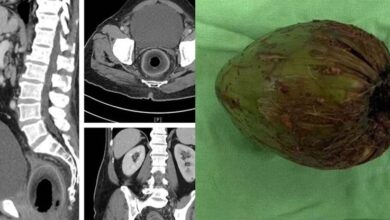

BIZARRO: Homem vai para em hospital após colocar COCO no ret0, disse q… Ver mais

Na noite abafada da última terça-feira (27), a rotina do Hospital de Emergência e Trauma Senador Humberto Lucena, em João…